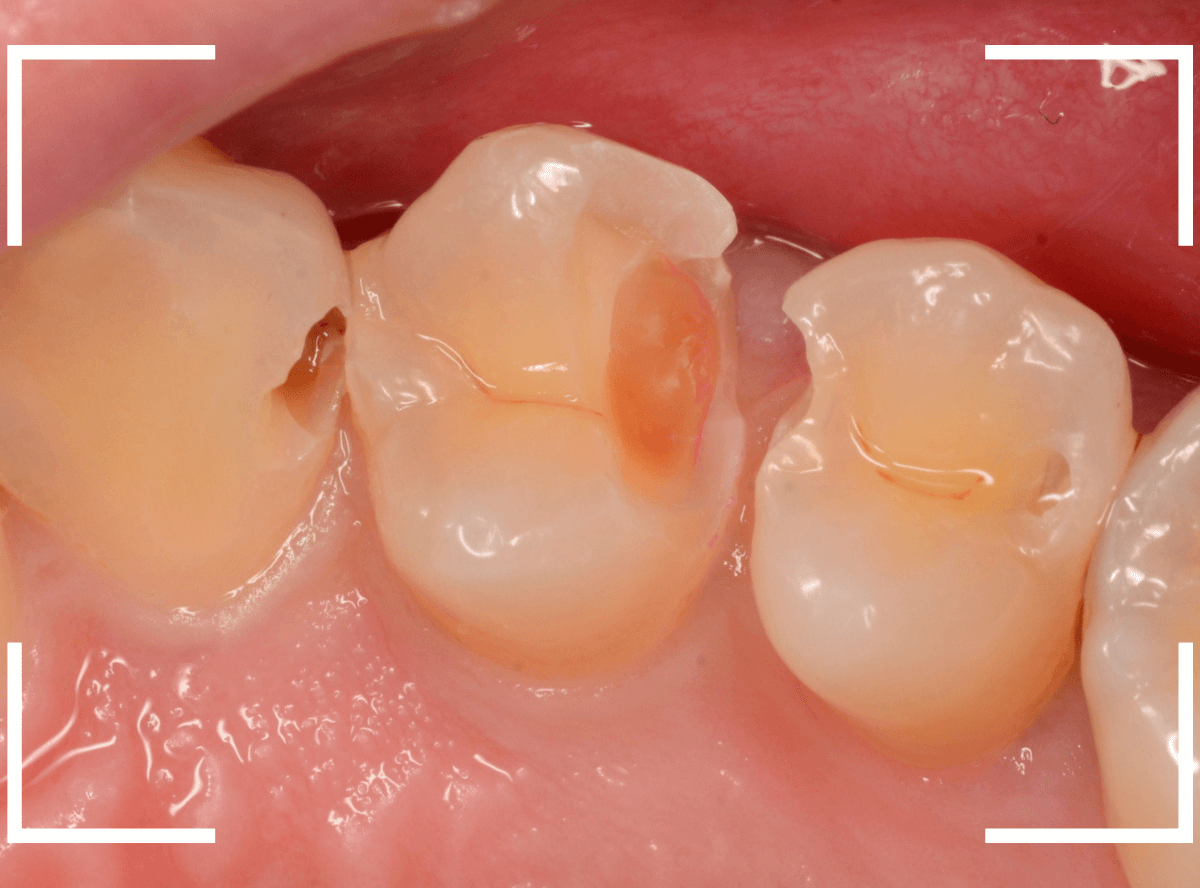

Case.22 痛みはないけど、歯のすきまから大きな虫歯

上の小臼歯の間が虫歯になっていた患者さんです。

症状はありませんし、見た目からも虫歯があるかはわかりませんでした。

レントゲン写真で確認します。

赤い線が虫歯、青い線が歯の神経です。

歯のすきまから両側に虫歯が大きく広がっているのが確認できます。

治療を開始します。

少し削ると、中からすぐに虫歯が出てきました。

ある程度、虫歯を除去したところで、う蝕検知液で確認します。

赤く染まっている部分が虫歯です。

まだまだ虫歯が中で残っている状況で、かなり深い虫歯なのが確認できます。

全ての虫歯を除去しました。

レントゲン写真からある程度確認出来ましたが、歯の神経スレスレまで虫歯が進行していました。

ここまで虫歯が進行していても、全く症状を感じない事も多いです。

そして、ある時急に痛みを感じるのです。

虫歯は急に進行しません。

治療後の定期検診で確実に食い止めましょう。